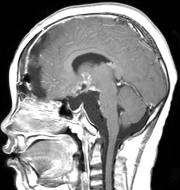

患儿入院后第三天,病情恶化,意识不清,急诊行肿瘤囊穿刺引流术,引流出囊液约200毫升,引流后患儿精神立即好转,肿瘤体积减小,引流手术切口设计及引流后CT见图7、图8。调养7天后在全麻下行开颅手术切除肿瘤,经过10个小时的努力,完全切除肿瘤,术后患儿清醒,语言交流正常,左侧上下肢肌力稍弱。患儿经历一系列的并发症,如电解质紊乱、脑水肿、癫痫发作等,共计住院47天后出院。术后CT见图9。

图8.肿瘤囊引流后体积明显变小

图9.术后CT显示肿瘤无残留。